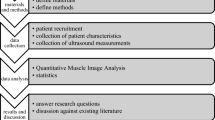

Study flow

Intra-and inter-rater reliability were assessed in the first 10 participants. The 1st session of muscle measurement was conducted by the primary investigator. The 2nd session was conducted one hour later by another investigator using the same scanning protocol, and the 3rd session was conducted by the primary investigator one week after the 1st session. The data derived from the 1st and 2nd sessions were used for analyses of the inter-rater reliability, whereas those of the 1st and 3rd were used for the intra-rater reliability. Examination of the remaining participants was carried out by the primary investigator. Both investigators were board-certificated dentists with more than one-year training in musculoskeletal US. All the participants were recruited based on their designated age (20–40, 40–60, > 60) and sex (female: male ratio = 1:1) stratification.